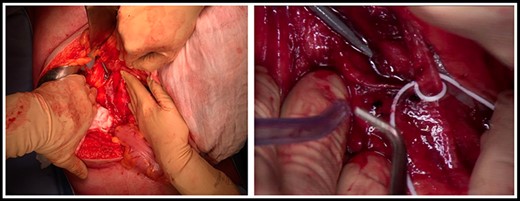

Intraoperative pictures showing the distal part of the probe outside the IVC.

Open repair was performed through a midline laparotomy. The Cattel-Braasch maneuver was carried out to expose the IVC. A retroperitoneal hematoma was observed anteriorly to the infrarenal IVC, without evidence of active bleeding. The IVC was prepared at the level of the left renal vein and at the bifurcation sufficiently to allow proximal and distal vascular control. The hematoma was then removed exposing the site of the perforation on the infrarenal IVC and the distal part of the probe outside the vein (Figure 2 a,b).